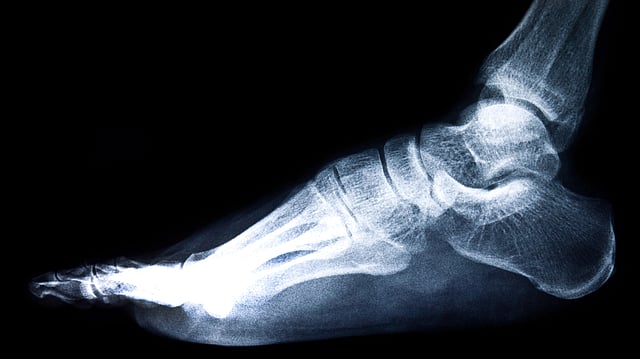

The Patel–Dhillon Classification provides exactly that, a structured way to assess what went wrong and how it can be corrected. Image by zirconicusso on Freepik

Doctors at the Postgraduate Institute of Medical Education and Research (PGIMER), Chandigarh, have developed a new method to classify ankle malunions, a condition where the ankle bone heals in a wrong position after a fracture. This new system, called the Patel–Dhillon Classification, was created by Dr Sandeep Patel, Associate Professor in the Department of Orthopaedics, and Dr Mandeep Singh Dhillon. Their research has been published in the Indian Journal of Orthopaedics.[1]

Ankle fractures are common, but when they do not heal properly, patients often face pain, stiffness, and difficulty walking. This incorrect healing, called malunion, happens when bones shift or rotate slightly during healing. Such deformities can also lead to arthritis and long-term mobility problems. Dr. Sandeep Patel, Associate Professor, Department of Orthopaedics, PGIMER, Chandigarh said to The Indian Express:

With new surgical methods, doctors can now correct the bone alignment while keeping the joint intact. But for that, a clear system was needed to describe the deformity, understand its severity, and guide the surgery. The Patel–Dhillon Classification provides exactly that, a structured way to assess what went wrong and how it can be corrected.[1]